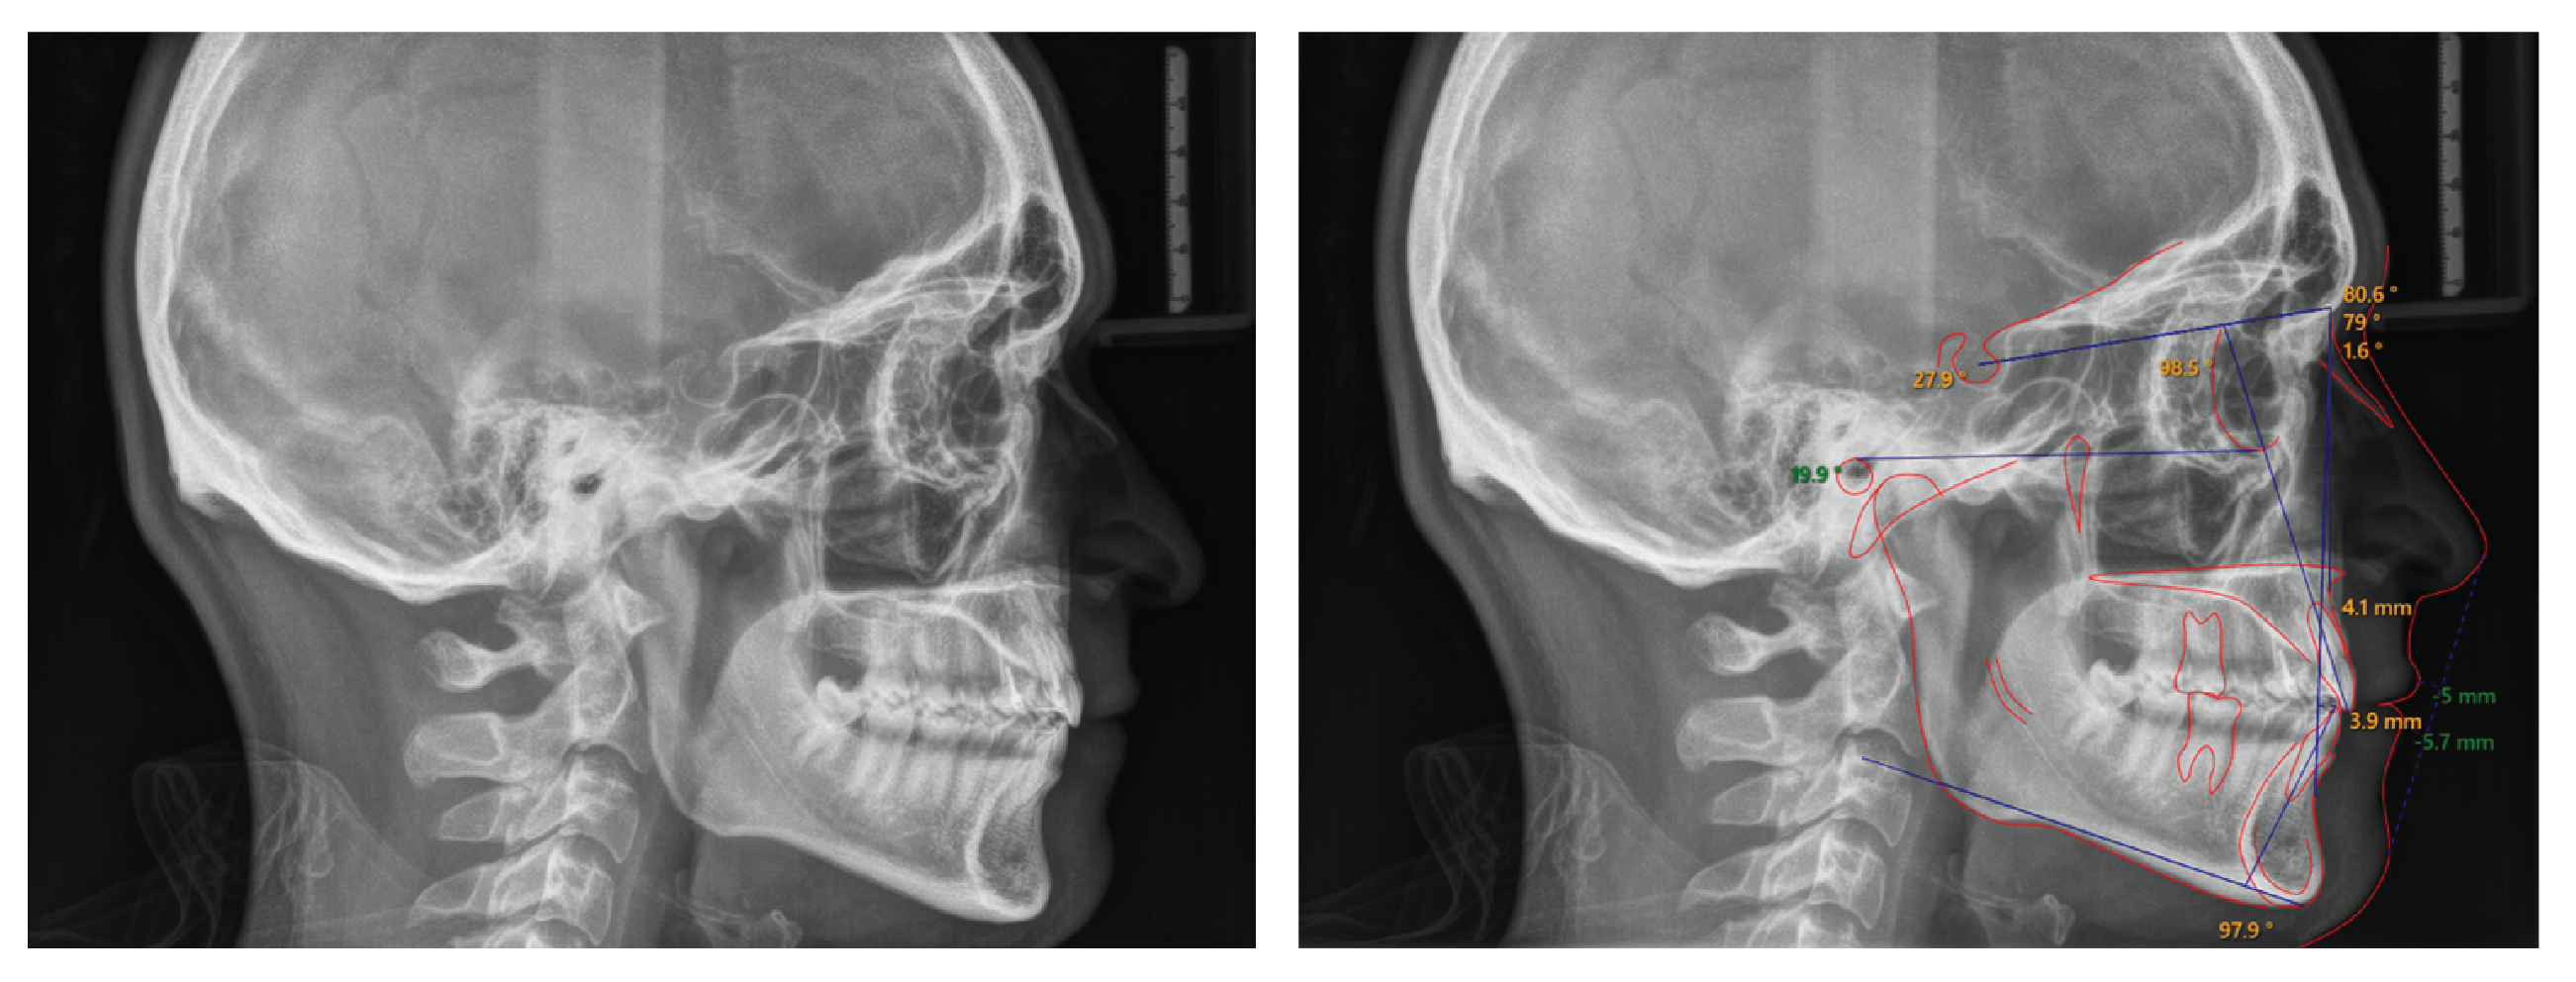

Lateral cephalometric analysis (Figure 8 and Table I) indicates that we maintained the sagittal (ANB = 1.6°) and vertical relation (FMA = 19.9°) of the jaws, and retroclined and extruded upper incisors.

Figure 8: Post-treatment lateral cephalometric radiograph. Post-treatment cephalometric radiograph shows an ideal overjet and overbite, slight retroclination of the maxillary incisors (98.5°) and minimal proclination of the mandibular incisors (100.2°). The sagittal and vertical relation of the jaws were maintained.